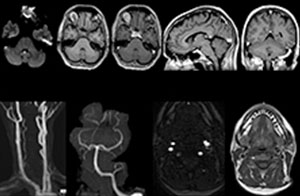

A range of protocol sheets was developed to help ensure that referring physicians order the most appropriate MRI exam. The optimized MRI protocols also include 3D contrast-enhanced imaging, allowing neurosurgeons to comfortably use the isotropic data in the operating room while performing stereotaxic surgery.